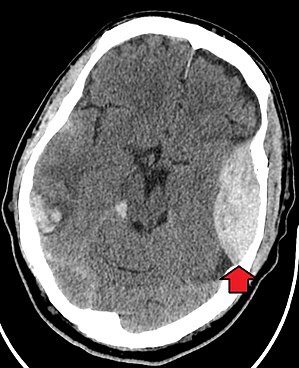

Epidural hematoma as seen on a CT scan with overlying skull fracture. Note the biconvex shaped collection of blood. There is also bruising with bleeding on the opposite side of the brain.

Epidural hematomas usually appear convex in shape because their expansion stops at the skull’s sutures, where the dura mater is tightly attached to the skull. Thus, they expand inward toward the brain rather than along the inside of the skull, as occurs in subdural hematomas. Most people also have a skull fracture.[3]